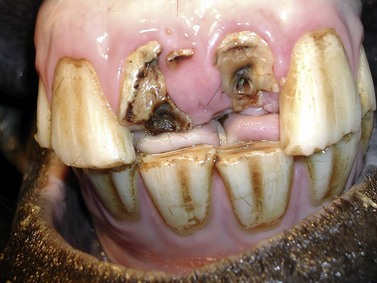

In the horse, provided occlusal contact is avoided, additional restorative covers may not be necessary over the calcium hydroxide,1 especially if covered with a resin-containing calcium hydroxide preparation. Alternatively, the more occlusal endodontic calcium hydroxide cement can be removed, and a few millimeters of the root canal close to the masticatory surface can be sealed with glass ionomere21 or a resin-composite endodontic material. In show horses, incisors that are fractured at gingival level can be reconstructed using parapulpar pins and composite (Figs 22.422.7) to avoid protrusion of the tongue. The owners should be informed that the reconstructed crown has to be reduced at intervals to prevent occlusal contact with the opposite incisor; otherwise the artificial crown will inevitably break as human parapulpar pins and composite cannot withstand the forces of equine prehension. Owners should also be advised not to feed hay from nets, in order to reduce forces on the incisor restorations.

image

Fig. 22.4 Longstanding (note necrosis of circumpulpar dentin) traumatic fractures of 101 and 201 in a 7-year-old horse. The fractured teeth have been cleaned. An isolated fracture fragment lying between 101 and 102 has been left in situ in order to prevent excessive local hemorrhage prior to endodontic therapy.